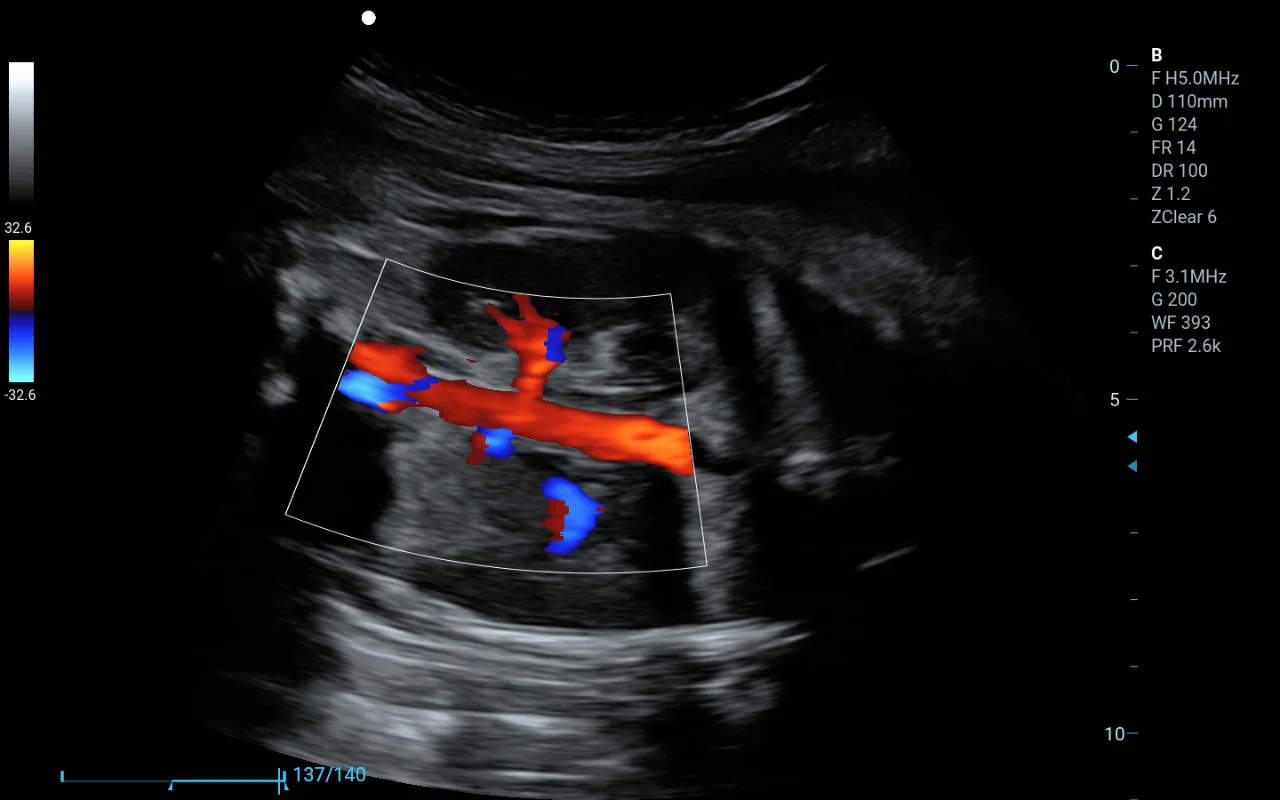

在醫院醫生可以利用這類軟件查看病人的CT或MRI影像,通過三維重建的圖像更直觀地判斷病變部位,這相當于給醫生提供了一雙“立體眼睛”,但最終的診斷還是由醫生來完成。這就是為什么它屬于第二類,而不是更嚴格的第三類醫療器械。